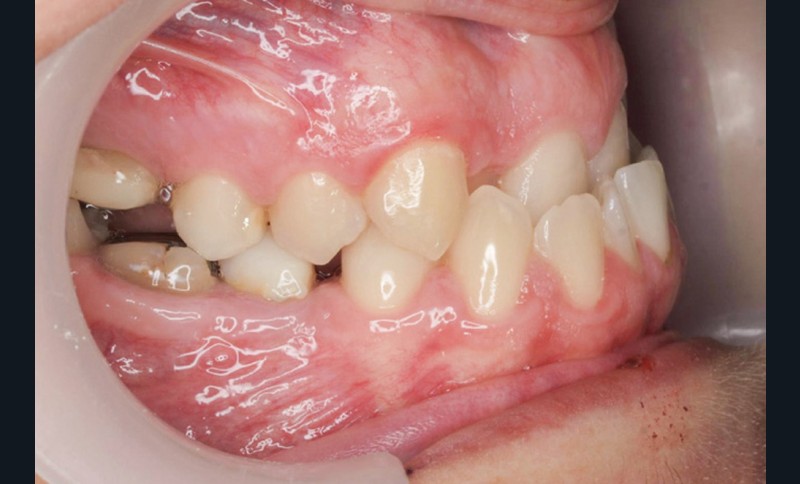

Diagnostic (fig. 1a-g)

La patiente présente une classe III squelettique dans un contexte hyperdivergent associée à une endoalvéolie maxillaire, un articulé inversé antérieur, une rétroversion incisive maxillaire, des rapports de classe I canine bilatérale, une absence de 16 et 36.

Au niveau esthétique, le profil est rectiligne. La lèvre supérieure est plus effacée, en retrait par rapport à la lèvre inférieure. De face et de profil, la mandibule paraît massive et le maxillaire effacé : le manque de soutien de la lèvre supérieure contribue à cette impression.

Le sourire est étroit, dégradé par les malpositions dentaires.

Au niveau fonctionnel, il existe un pro-glissement mandibulaire et un articulé inversé antérieur. Le profil téléradiographique montre en occlusion des rapports labiaux et un profil de classe III plus marqué que sur photographies.